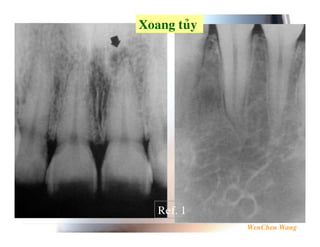

23 . 4 5 6 % 6 , 6 Ref. 1

5 .7 Ref. 1

5 %$ Ref. 1